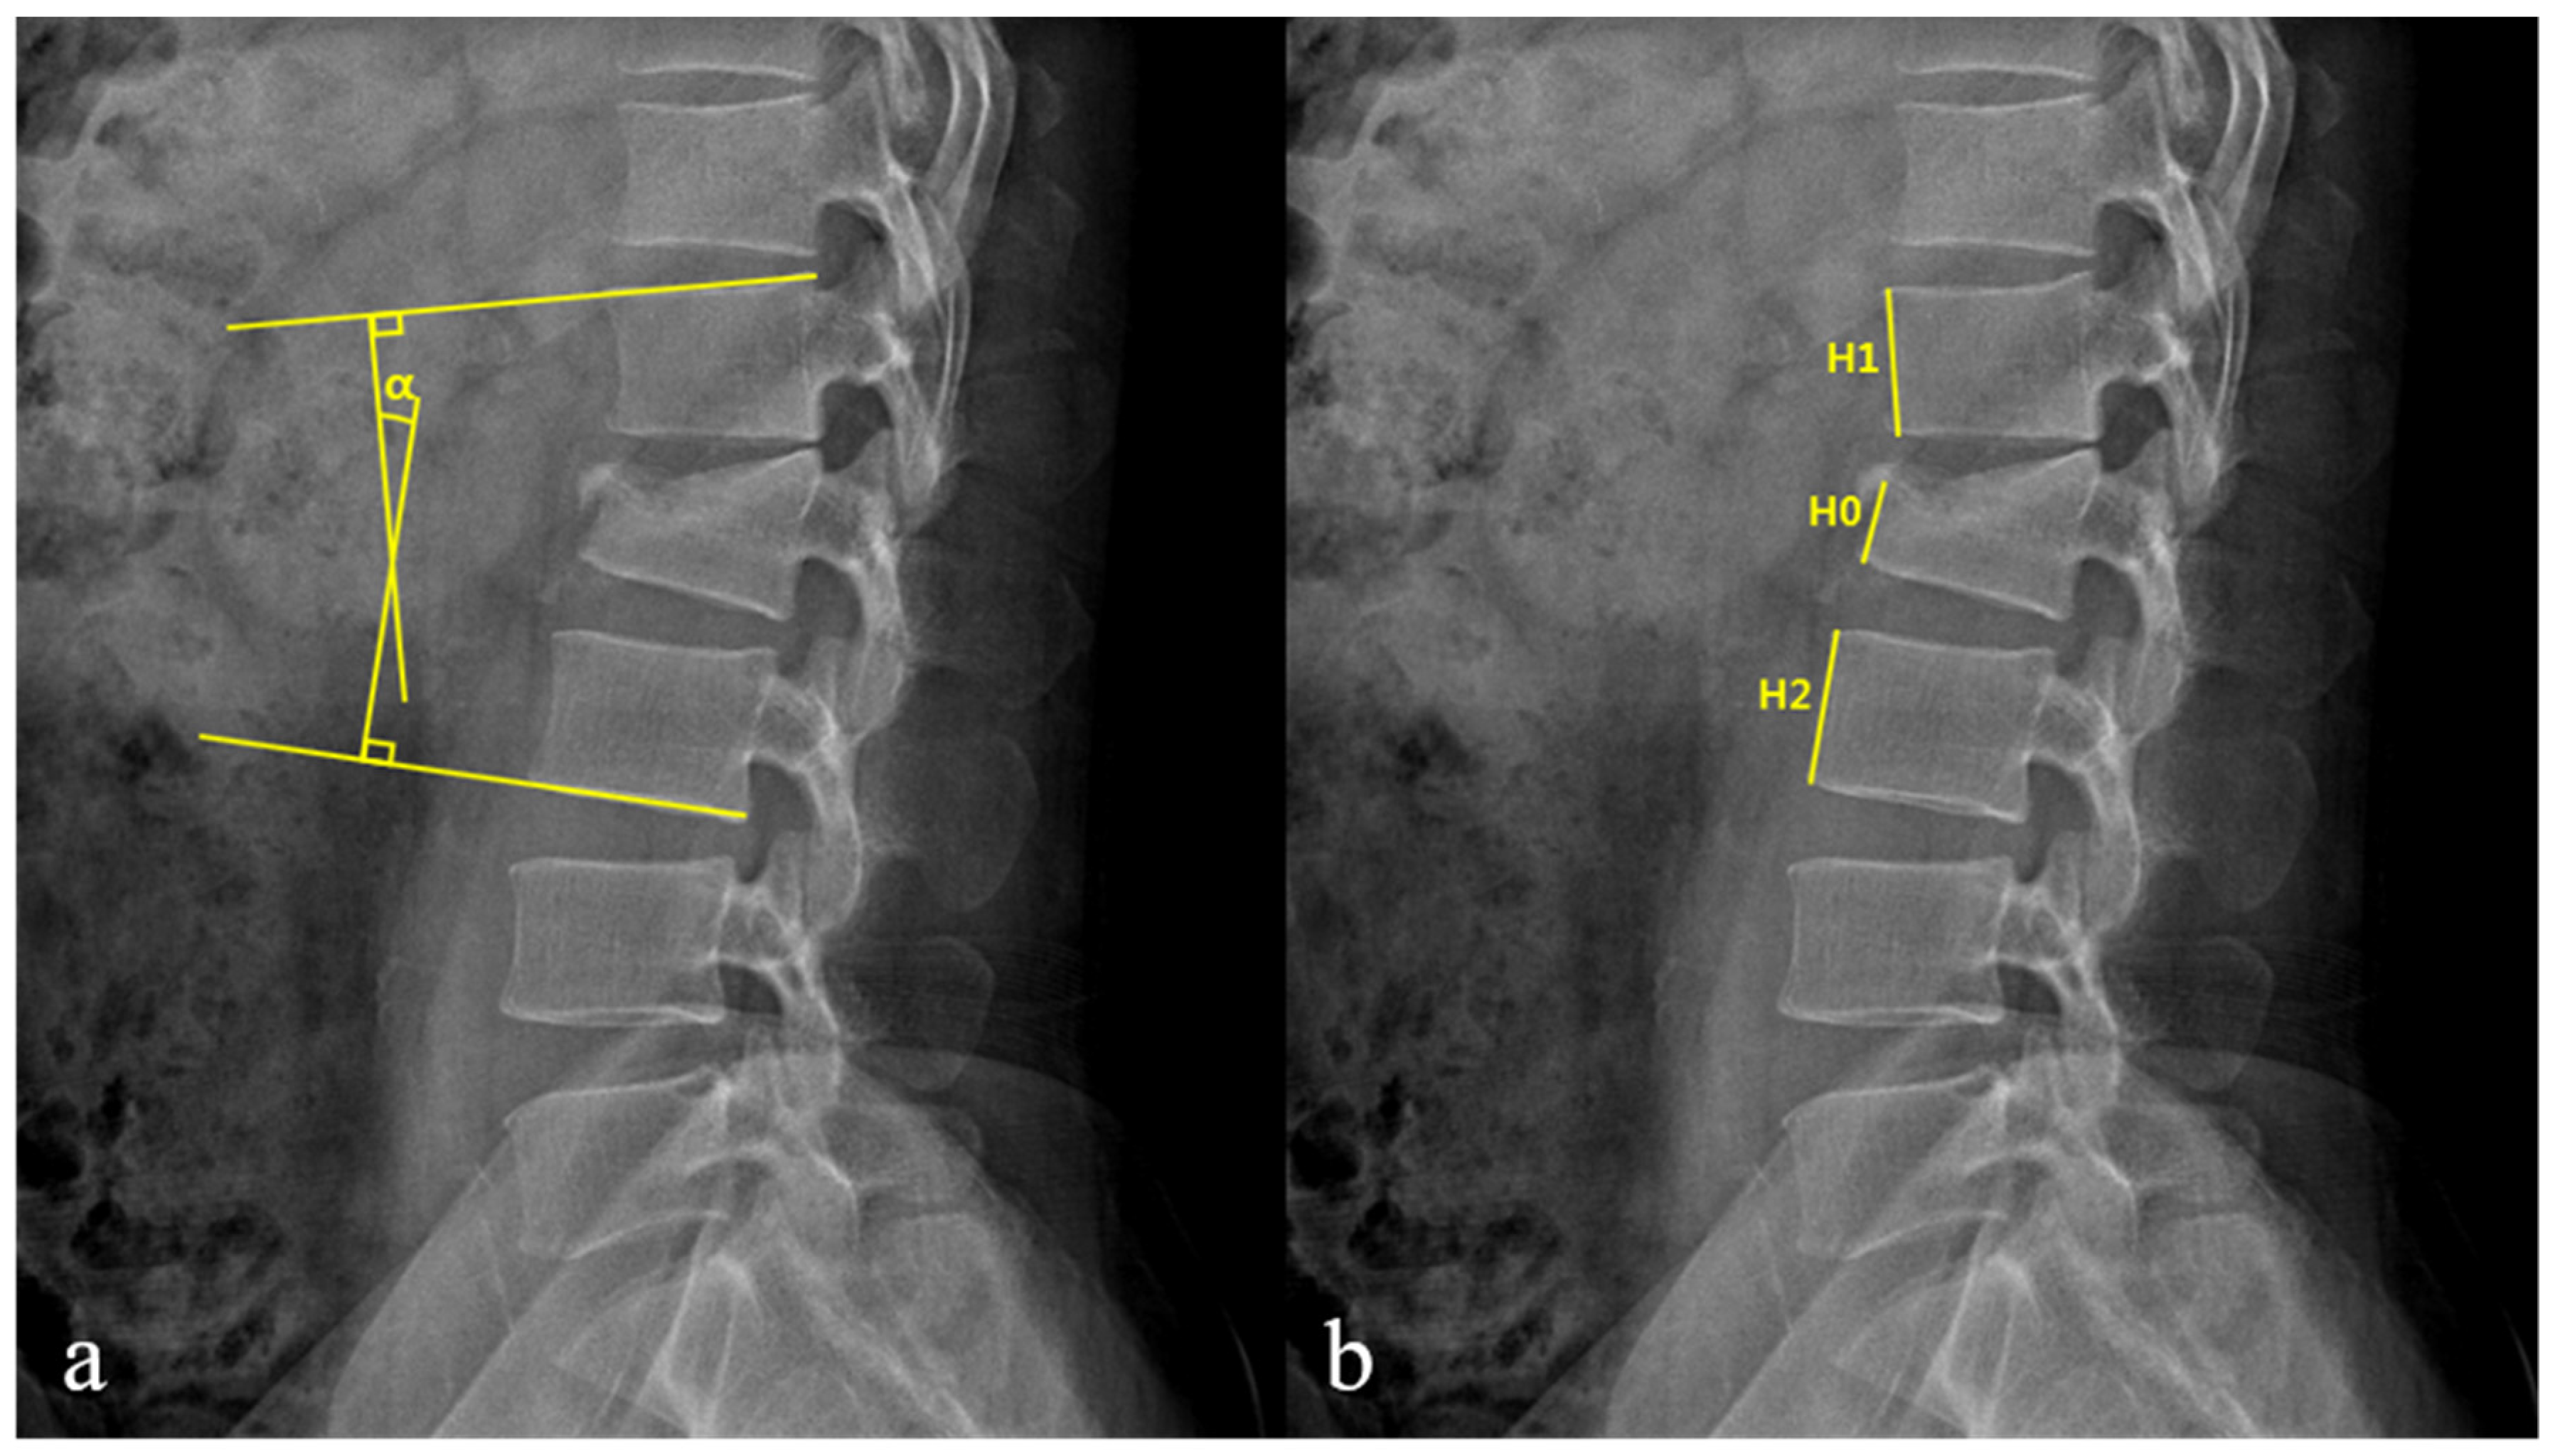

| Loss of vertebral body height (%) ‡ | 28.6 ± 7.8 | 34.1 ± 6.0 | 0.01 |

| Kyphotic angle (°) ‡ | 10.1 ± 6.2 | 13.9 ± 5.0 | 0.04 |